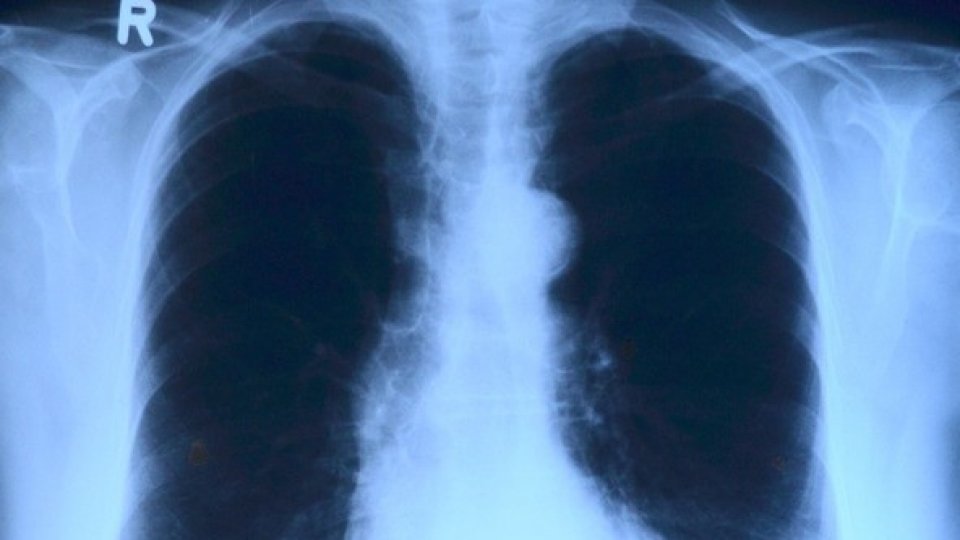

Numărul bolnavilor de tuberculoză la nivel mondial este în creştere, atrage atenţia Organizaţia Mondială a Sănătăţii. În ţara noastră, creşterea are drept cauze, spun specialiştii, lipsa resurselor medicale şi diagnosticarea întârziată.

Dragoş Dendrino: „Cum facem asta? Cu patru caravane care sunt dotate cu aparate de radiologie de ultimă generaţie. Avem cel mai mic cabinet de radiologie din câte sunt şi utilizăm un soft care citeşte radiorafia instant cu inteligenţa artificială. Pe loc primim un scoring, probabilitate ca în imaginea respectivă să existe sau nu tuberculoză.”